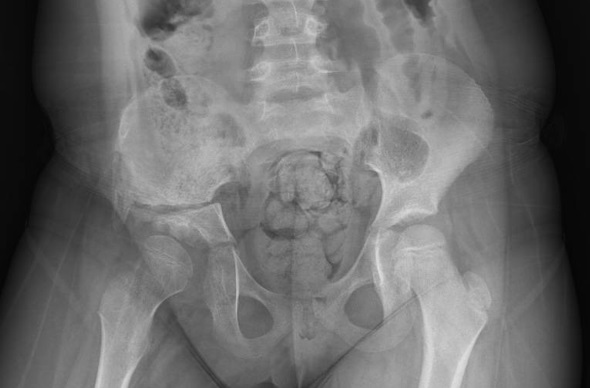

La displasia de cadera es una afección frecuente -afecta entre 1 de cada 100 a 1 de cada 1000 niños- que, diagnosticada a tiempo, puede corregirse con tratamientos ortopédicos sencillos y evitar secuelas graves a largo plazo. Recientemente, el doctor Díaz y equipo de Traumatología de Quirónsalud Málaga ha operado a una niña de seis años con síntomas y limitaciones en la vida diaria, como cojera y dolor con la deambulación, así como cambios a nivel de la cadera que ya no se podían corregir con tratamiento conservador", comparte el traumatólogo.

Tras ser valorada por el Dr. Díaz y ante los cambios estructurales irreversibles en la articulación de la paciente, determinó la necesidad de una intervención quirúrgica. "Este caso nos recuerda que un diagnóstico y tratamiento correctos y tempranos son esenciales para permitir un desarrollo normal de la cadera y prevenir complicaciones futuras".